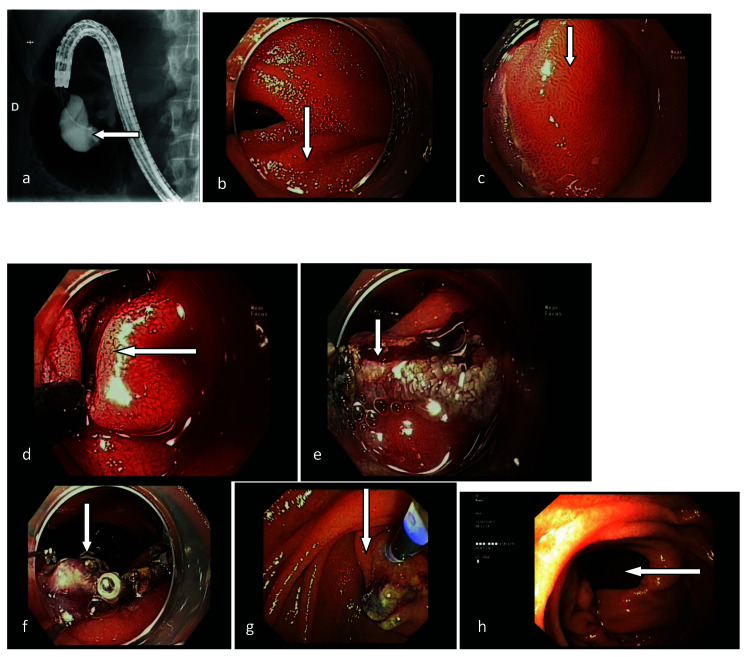

Intraluminal duodenal diverticulum is a rare entity that may cause recurrent pancreatitis. We report a case of a 36-year-old female admitted with etiologically unclear, recurrent pancreatitis. Radiographic study and endoscopy revealed a sac-like structure of the second portion of the duodenum near the minor duodenal papilla. Endoscopic diverticulotomy was successfully performed. No complications were observed and the patient was discharged home a day later. After 62-month follow-up, the patient was active and without symptoms. To our knowledge, this is the first reported case of recurrent pancreatitis caused by intraluminal duodenal diverticulum near the minor duodenal papilla, treated with endoscopic diverticulotomy performed from the apex to the base of the diverticulum.